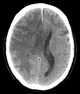

Venous cerebral infarction

Cerebral venous sinus thrombosis (CVST) is the presence of a blood clot in the dural venous sinuses, which drain blood from the brain. Symptoms may include headache, abnormal vision, any of the symptoms of stroke such as weakness of the face and limbs on one side of the body, and seizures. [Source: Wikipedia ]